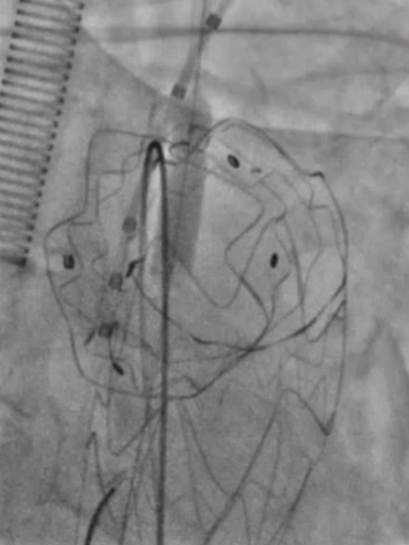

★ 左锁骨下动脉重建

从左侧肱动脉导入可调弯鞘送至左锁骨下动脉近端,同样使用asahi treasure 12导丝和支撑导管顺利通过覆膜区。依次送入4mm、6mm和8mm球囊对局部进行扩张。

将支架送入覆膜区约1cm释放支架。之后,更换更大口径的球囊送至主动脉弓内进行后扩张,使支架呈喇叭口状,以稳定两者结构,减少内漏的发生。由于左锁骨下动脉位于假性动脉瘤的破口位置,此处使用球扩覆膜支架实现了更加精准的定位,有效降低了内漏风险。

球囊回收时

带鞘进开窗口

置入VBX11-29mm支架,支架伸入

覆膜支架约1cm后释放并球扩塑形